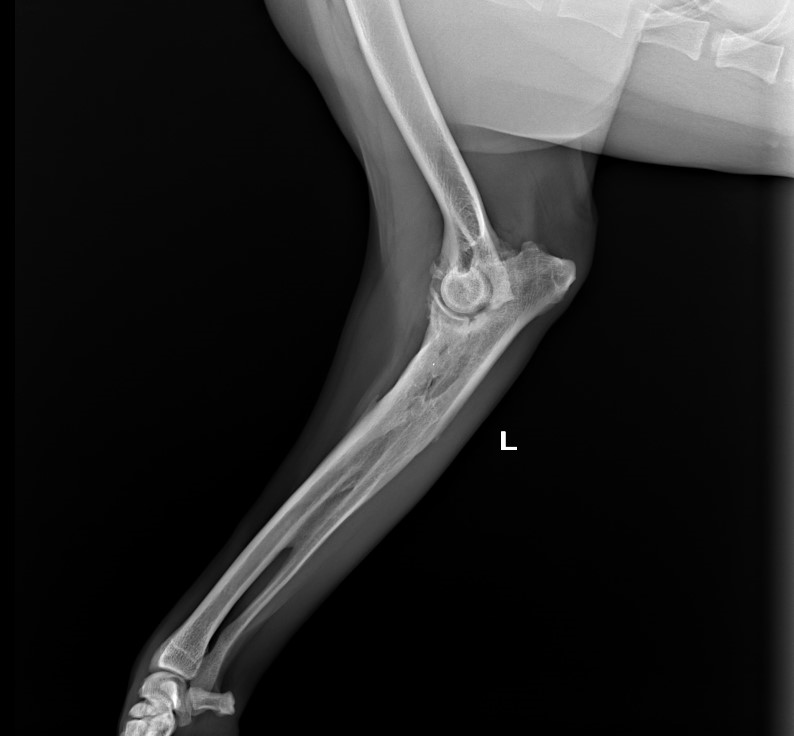

Radioulnar Synostosis

Female, 7.5 yo, 27 kg, mixed breed dog

presented with chronic 2 grade left forelimb lameness

Orthopedic examination did not detect abnormalities, x-ray with awake patient was performed on forelimb (medio-lateral view of elbows and dorso-palmar view of carpus).

Diagnosis of severe left Elbow Dysplasia with radio-ulnar synostosis presumably

as a result of an old fracture.

conservative treatment was proposed with NSAID in acute phase (carprofen), PEA, controlled activity and weight management.

On follow-up owner reported good response to proposed protocol.